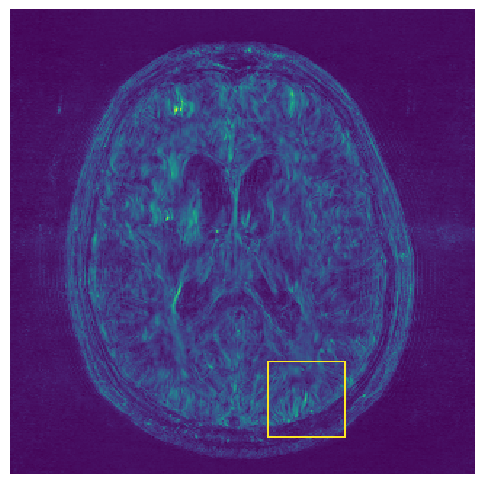

(e) Std.

Figure 3: Examples of Reconstruction Results. Rows 1 and 3: The Ground truth (GT) fully sampled image, the reconstructed images obtained by the three models (1-3), NPB-REC, baseline, E2E-VarNet trained with Dropout, and the Std. map derived from our method for acceleration rates R=4𝑅4R=4, R=8𝑅8R=8, respectively. Rows 2 and 4: The corresponding annotated ROIS of the edema and resection cavity.

Fig. 3 presents examples of reconstruction results obtained by (1) our NPB-REC approach, (2) the baseline, and (3) Monte Carlo Dropout, for equispaced masks with two different acceleration rates R=4𝑅4R=4 and R=8𝑅8R=8. Table 1 presents the mean PSNR and SSIM metrics, calculated over the whole inference set, for the three models. our NPB-REC approach achieved significant improvements over the other methods in terms of PSNR and SSIM (Wilcoxon signed-rank test, pmuch-less-than\ll1e-4). The improvement in the reconstruction performance can be noted both quantitatively from the metrics especially for masks with acceleration rate R=8𝑅8R=8 and qualitatively via the images of annotations, where our results shows less smoothness than that obtained by Dropout.